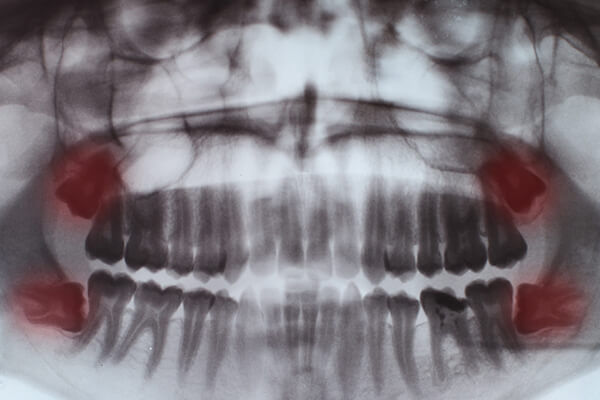

Recomendado 100% me realice la cirugía de cordales, cero dolor Una excelente atención, poca inflamación y rápida recuperación.

Excelente cirujano 100% se los recomiendo pues me saque dos cordales y no hubo dolor en el procedimiento y una rápida recuperación ??

Tiene buena mano el Dr. La extracción de cordales fue sin dolor. Buena recuperación.